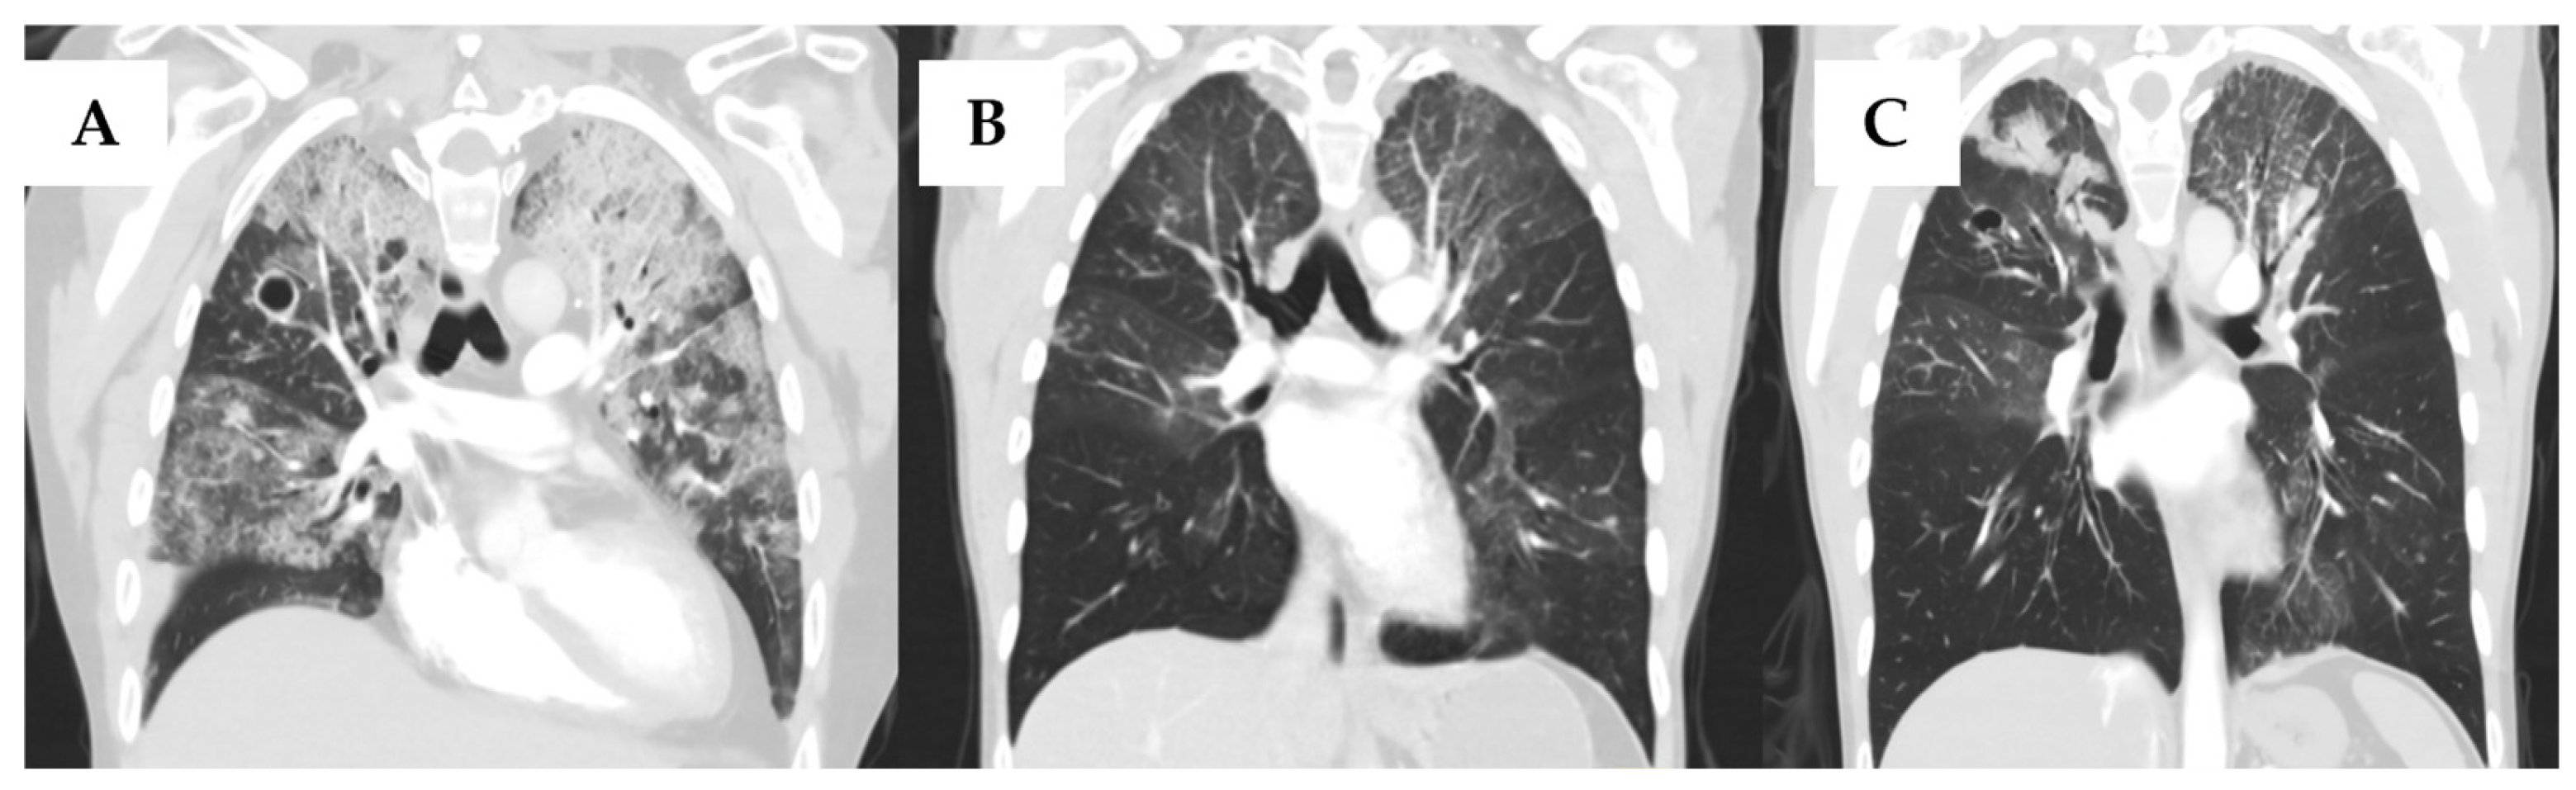

A 42-year-old woman underwent a 10/10 HLA-matched sibling peripheral blood stem-cell transplant for FLT3-ITD-positive acute myeloid leukemia after first achieving complete remission with 7 + 3 induction and one cycle of high-dose cytarabine consolidation. Conditioning was myeloablative busulfan and cyclophosphamide. On post-stem cell transplant day (PSCTD) day 134, she developed moderate chronic GVHD (cGVHD) of the mouth, skin, liver and eyes. Over the following year, this evolved into severe pulmonary cGVHD and, over time, pulmonary chronic graft-versus-host disease progressed, with the development of bronchiolitis obliterans that ultimately evolved into severe end-stage lung disease, necessitating therapy with prednisone at 1 mg/kg, mycophenolate mofetil, azithromycin, umeclidinium/vilanterol and montelukast. Her infectious prophylaxis regimen included acyclovir 400 mg twice daily, penicillin V 300 mg twice daily, posaconazole 300 mg delayed-release daily, and trimethropirm-sulfamethoxezaole (one double-strength tablet three times weekly). Five years after HSCT, she experienced worsening respiratory symptoms and the development of cavitary right upper-lobe lesions warranting serial bronchoscopies that yielded Mycobacterium chimaera together with Microascus spps. and a positive serum galactomannan. Antimicrobial therapy was initiated, which included 12 weeks of intravenous amikacin, azithromycin, and ethambutol, which was later substituted with Moxifloxacin due to her underlying eye GVHD) and rifampicin, followed by clofazimine and 12 months of rifabutin, substituted due to liver toxicity and Mycobacterium chimaera resistance pattern. The microascus infection treatment regimen included 12 weeks of voriconazole, and inhaled and intravenous liposomal amphotericin B for Microasuas species. Management was repeatedly interrupted due to adverse events including hepatotoxicity with rifampin, visual concerns with ethambutol and pronounced QTc prolongation to 628 ms, necessitating temporary cessation of clofazimine and rifabutin. Near-complete clinical and radiological resolution was reported on repeated imaging 3 months after extensive treatment, with subsequent bronchoalveolar lavage samples negative for NTM (Figure 1).

Figure 1.

Computed tomographic (CT) scans of the lung of a 42-year-old female with nontuberculous mycobacterial infection (NTM) and non-Aspergillus invasive mold infection (NAMI) in a hematopoietic cell transplant recipient, who subsequently received bilateral lung transplantation. (A) Multifocal ground-glass opacities more prominent in the left lung; 1.5 cm cavitary lesion in the right upper lobe with centrilobular nodularity reported prior to NTM and NAMI therapy initiation. (B) Near-complete clearing of severe bilateral airspace consolidations after treatment of Microascus spp. and Mycobacterium chimaera infections. (C) Bilateral consolidative changes in the upper lobes, mostly at the time of diagnosis of Aspergillus calidoustus infection.